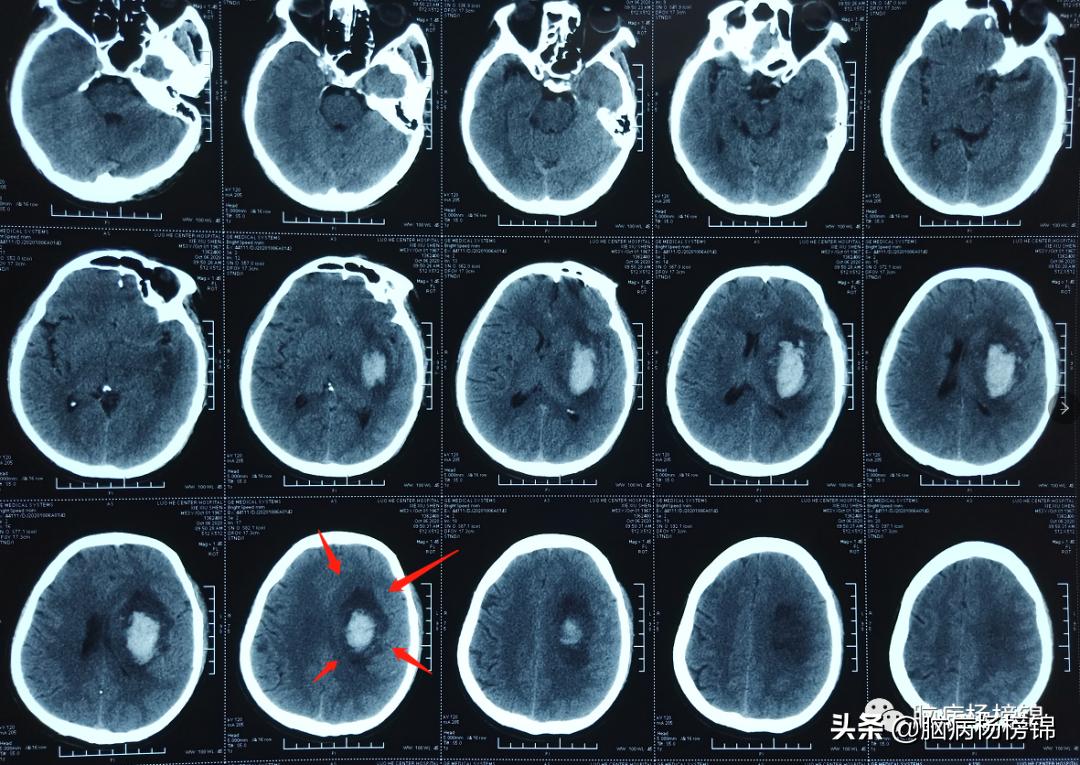

保守治疗16天,血肿开始吸收。